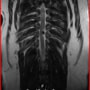

■ MRI検査

第5-6腰椎間で右側神経根が腫大し、脊柱管内に連続した腫瘤病変が認められました。脊髄および馬尾神経は右側から重度に圧迫されていました。

MRI検査所見

MRI 1